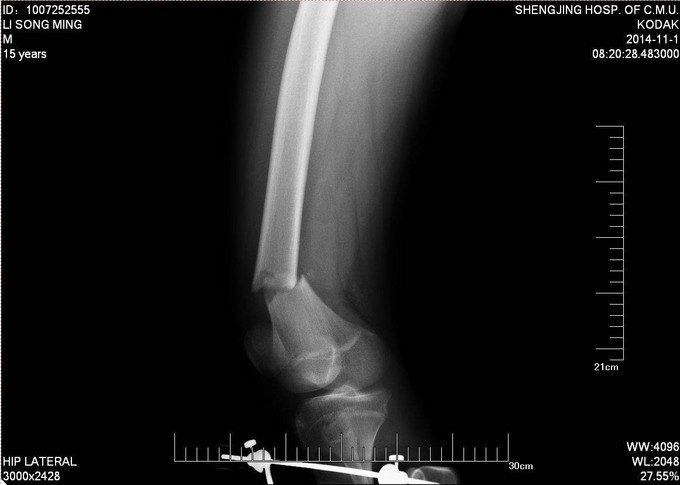

患者及家属自述于2014年10月31日,在学校与同学打闹过程中不慎别伤,伤后自觉右大腿疼痛伴有活动受限,就诊于当地医院行股骨正侧位X线片提示:右股骨远端骨折。未于治疗。后患者为求进一步诊治来我院急诊就诊,请我科会诊后,诊断为右股骨远端骨折,建议手术治疗,收入病房。伤来饮食、睡眠欠佳。大小便正常,体重无明显变化。

专科查体:见右大腿肿胀,畸形。大腿远端压痛阳性,轴向叩击痛阳性,可触及骨擦音,骨擦感。见双足高弓扬趾,右侧足背伸肌力5级,足背动脉可触及。

诊断:右股骨远端骨折 患者入院后急诊行生化检查等,查无手术禁忌症后急诊行右胫骨结节骨骼牵引术,维持患肢长度,减轻患者疼痛后,完善相关检查,请相关科室会诊后,查无明显手术禁忌症后行右股骨远端骨折闭合复位Liss钢板内固定术。